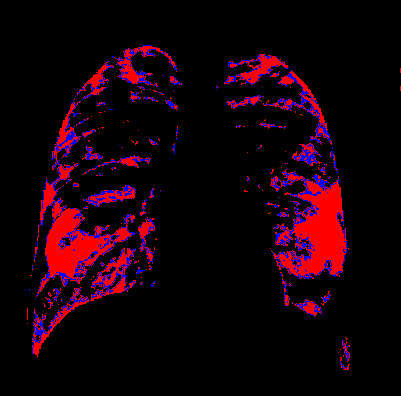

Side-by-side inspection of the generated healthy counterfactuals (as per fig. 2) suggests that, as required, only minimal perturbation is made to the original image with respect to healthy pixels -i.e. localized image sites without structural medical defects. (In the top row, the medical structural defect in the original image is due to a lung opacity, and characterized via a relatively complex interaction between the imaging modality and subject manifesting as ‘gaps’ in the corresponding portions of the lung scan). The healthy/non-healthy discrepancy maps in all of these cases are obtained via masked subtraction of the original image from the generated image (the ground truth segmentation masks correspond to the broad area of interest –i.e. the complete lung). The generated healthy tissue is thus a subset of the mask and is shown in the final column of fig. 2 for the respective cases.

In the context of a VANT-GAN[20]-based approach, this highlighted material constitutes the diagnostic counterfactual visual attribution, i.e. the selection of material relevant to the diagnosis of the unhealthy condition. Healthy counterfactual generation was performed for the complete datasets in the three unhealthy classes, i.e Lung opacity, Viral Pneumonia and COVID, examples of which are given in fig. 3 for the three classes (all of the generated healthy counterfactuals from this experiment can be found on https://huggingface.co/ammaradeel/diffusionVA). Visual inspection indicates that the generated counterfactuals are, in general, visually plausible with minimal perturbation made to the unhealthy image overall. Moreover, the healthy counterpart generation does not appear to unnecessarily affect aspects of the images unrelated to the medical condition, the model selectively making changes to the unhealthy regions in a structurally plausible manner, e.g. generating missing portions of the lung without generating extraneous lung material where it would be expected to normally exist (e.g. in the abdominal cavity).